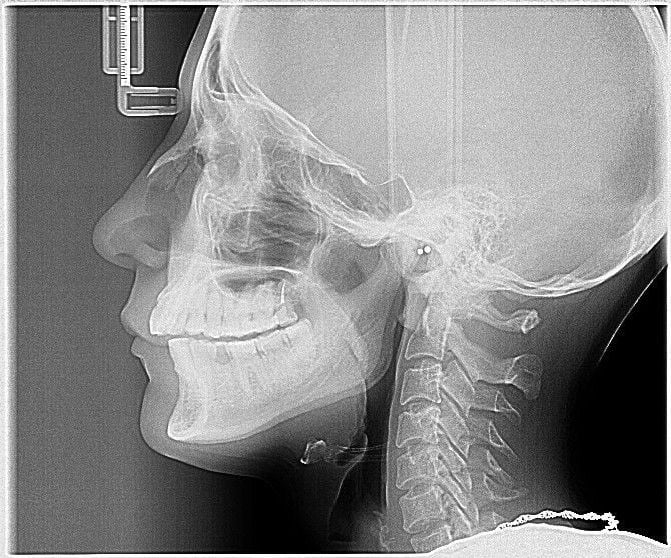

Для определения стадии развития заболевания, его локализации чаще других используется рентгенография. Рентгеновский снимок позволяет увидеть возникшие деформации, разрастания костей, изменения их формы. Реже применяются КТ, электромиография, контрастная рентгенография или брекеты (ортодонтические скобы).